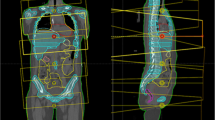

A model TMI planning was conducted in the solid water phantom of 110 (length) × 15 (width) × 8 (depth) cm3 in which dummy bone marrow structure (PTV) and organs at risks such as lung, kidney, and body subtracting from target were contoured (Figure 1).

For dose verification, two ion chambers at 2 cm depth were put at 27.5 cm and at 72.5 cm from tip of the phantom at SAD = 85 cm (Figure 1). Two EDR-2 films (Kodak, Rochester, NY, USA) were also placed in a line in the phantom from 25 cm to 85 cm from the tip. Film analysis was performed in delivery quality assurance workstation and the comparison of longitudinal profile and gamma analysis with the criteria of 3 mm/3% between planned and measured dose were performed.